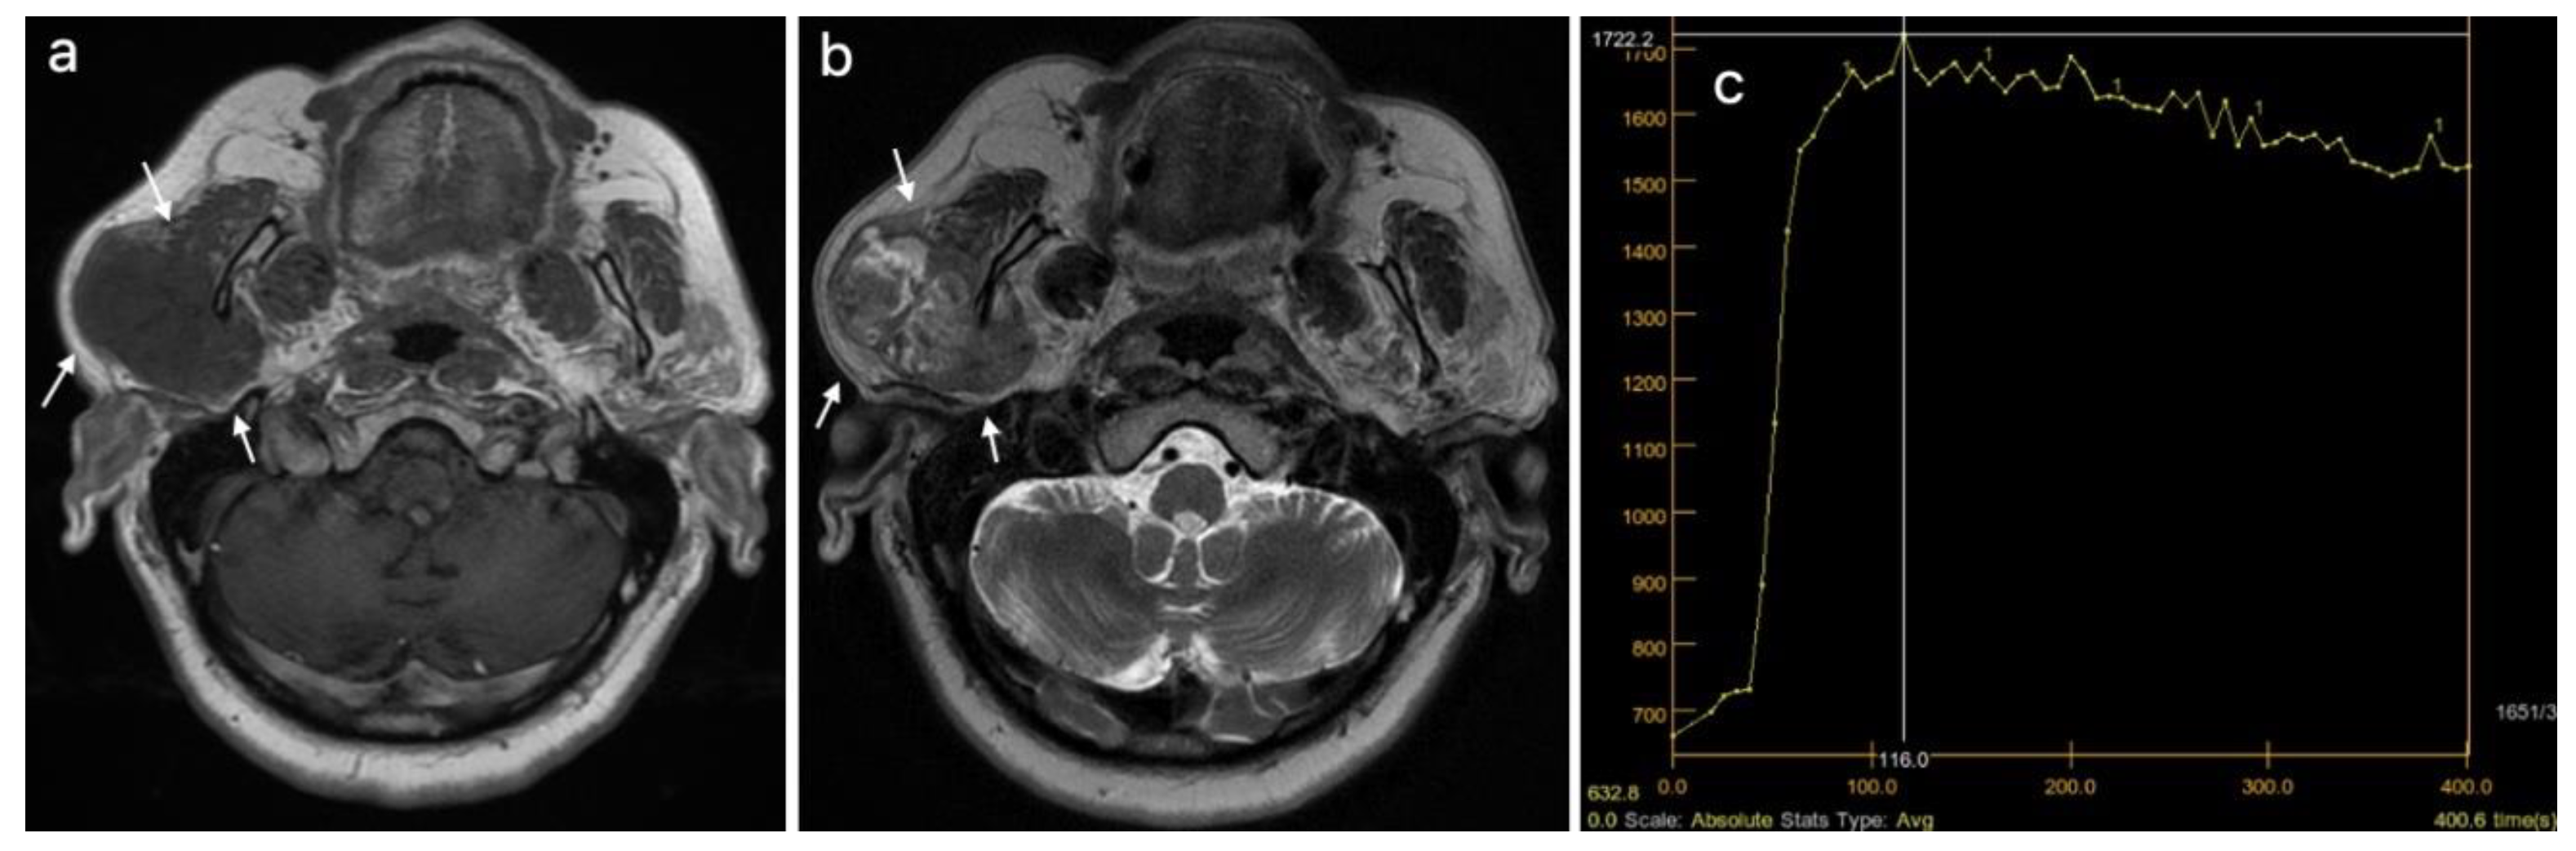

| DCE MRI*–TIC curve+, n (%) | 0.382 | ||

| Type A | 16 (29.63) | 1 (9.09) | |

| Type B | 18 (33.33) | 5 (45.45) | |

| Type C | 20 (37.04) | 5 (45.45) | |

| DCE MRI, TIC curve grouped (A, B vs. C), n (%) | 34 (62.96) | 6 (54.5S5) | 0.737 |

| DCE MRI, TIC curve, n (%) | <0.001 | ||

| Type B | 3 (15.79) | 11 (37.93) | |

| Type C | 1 (5.26) | 18 (62.07) | |

| DCE MRI, TTP (ms), median (IQR) | 210 (166.15–228.9) | 88.5 (82–101.9) | <0.001 |